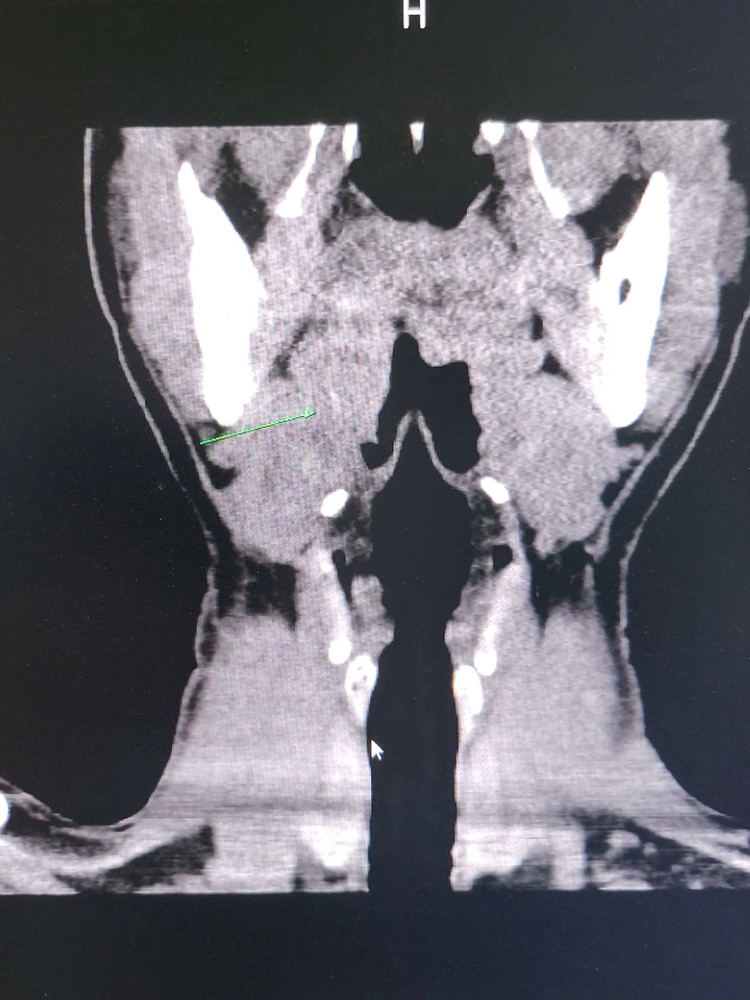

Hình ảnh xương cá trên phim chụp của bệnh nhân.

Kết quả khám nội soi thông thường không thấy có hình ảnh nghi ngờ dị vật, vùng hạ họng amidal bên phải tương đối bình thường nên các bác sĩ đã quyết định chụp phim cắt lớp vi tính vùng cổ, không tiêm thuốc cản quang. Trên phim CT Scanner vùng cổ chỉ thấy có một lát cắt Coronal và tái tạo dựng hình 3D có hình ảnh nghi ngờ có dị vật là một vệt mờ, khó xác định ở vùng amidal ở bên phải.